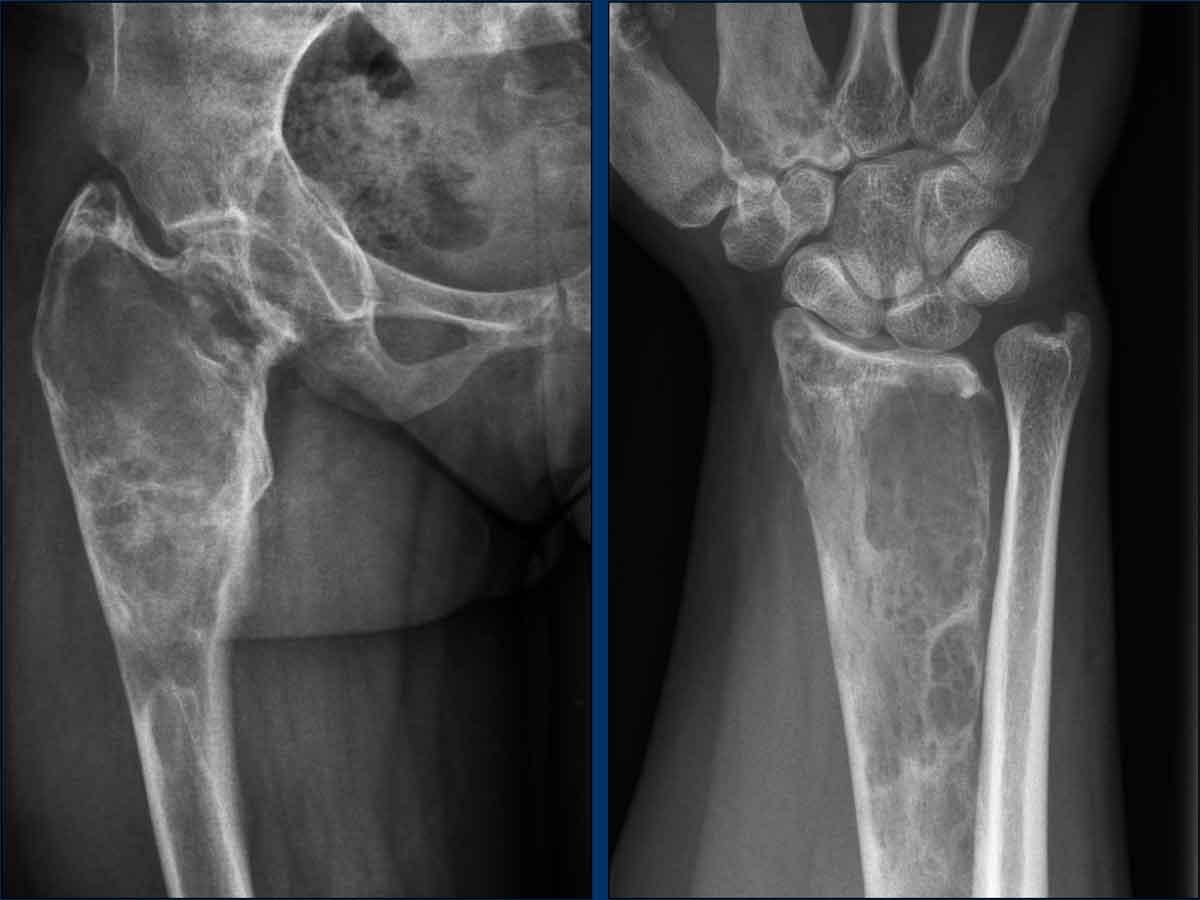

Hông

Có sự giãn nở của đầu trên xương đùi với sự mở rộng của hành xương và tổn thương tiêu xương dạng kính mờ với bờ xơ cứng trong ống tủy. Lưu ý tình trạng thoái hóa khớp háng thứ phát.

Cổ tay

Đầu dưới xương quay có hình ảnh tương tự với cấu trúc xương bị thay đổi do các tổn thương tiêu xương dạng kính mờ kèm giãn nở. Xương đốt bàn tay thứ nhất và thứ hai cũng bị ảnh hưởng.

Kết luận

Tổn thương đa xương kết hợp với tuổi tác, tiền sử dậy thì sớm và hình ảnh X-quang làm cho trường hợp này mang tính chất đặc trưng bệnh lý của loạn sản xơ xương (FD).

Không nên thực hiện sinh thiết.

Bệnh nhân này được biết đến với chứng loạn sản xơ đa xương như một phần của hội chứng McCune Albright.